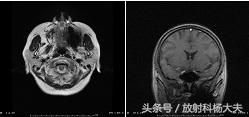

伪影较重的假牙图像

上文中可以发现,在伪影较重的图像中,DWI图像受到了严重的影响,不利于疾病的诊断与鉴别诊断。